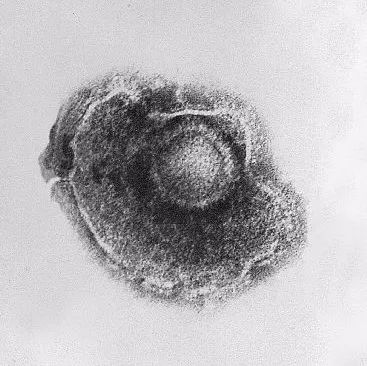

它们都是由同一种水痘-带状疱疹病毒(varicella zoster virus,简称VZV)引起的感染。而这种病毒广泛分布在全世界,人类是它唯一的宿主。

电子显微镜的水痘带状疱疹病毒约放大倍数为150,000倍

水痘-带状疱疹病毒(VZV病毒)也总会不经意入侵到我们的身体内。